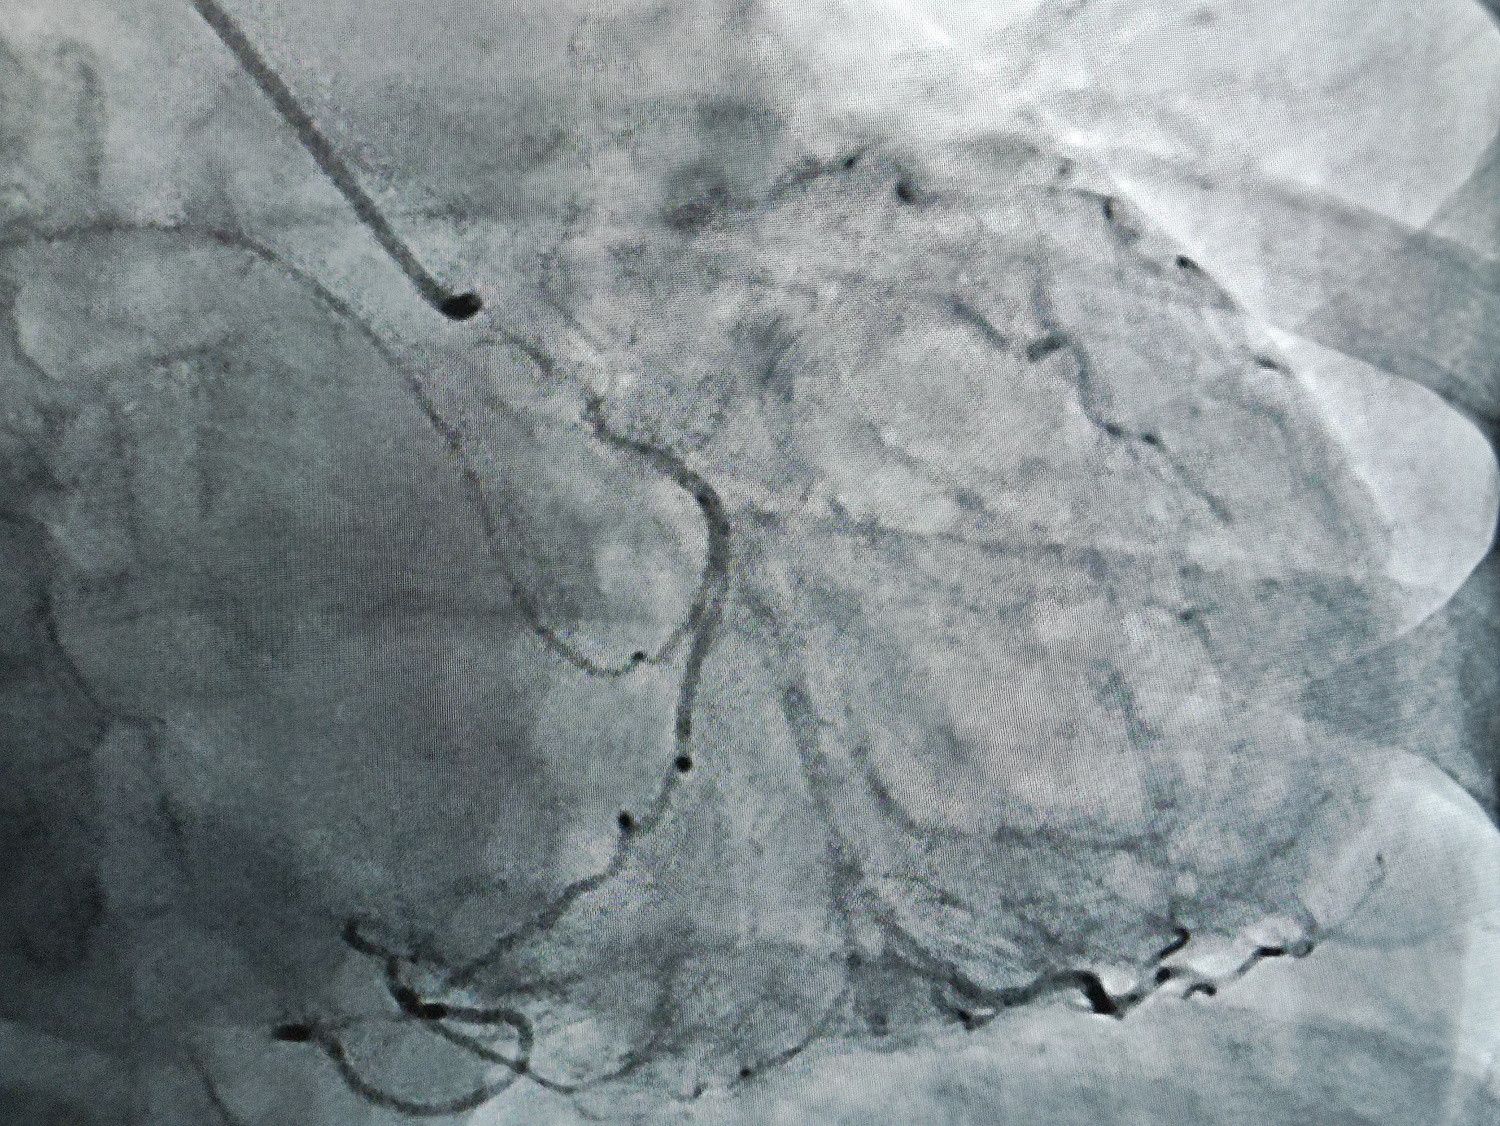

Новое оборудование представляет собой высокотехнологичный комплекс, с помощью которого под воздействием рентгеновского излучения можно визуализировать просвет сосудов, полостей сердца и кровоток. Это позволяет врачам выявлять такие патологии, как закупорки, сужения сосудов, тромбы, аневризмы, оценивать целостность и структуру сосудистой стенки и мн.др. На основе полученных данных можно максимально точно поставить диагноз, определить локализацию и характер поражения, а также спланировать и провести дальнейшее лечение, включая малотравматичное хирургическое вмешательство.

Первую коронарографию пациентке с ишемической болезнью сердца 4 сентября выполнил врач по рентгенэндоваскулярным диагностике и лечению отделения РХМДЛ, к.м.н. Евгений Андреевич Глухов.

«В ходе ангиографического исследования с помощью катетера в сосуд вводят йодосодержащее рентгеноконтрастное вещество, которое не пропускает рентгеновские лучи и, смешиваясь с кровью, делает просвет сосуда видимым под рентгеном, - рассказал Евгений Андреевич. - Например, при ишемической болезни сердца исследованию подвергаются коронарные сосуды, поэтому данную разновидность исследования называют коронарографией. При необходимости ее сочетают с эндоваскулярными или внутрисосудистыми видами хирургических вмешательств – стентированием, ангиопластикой».